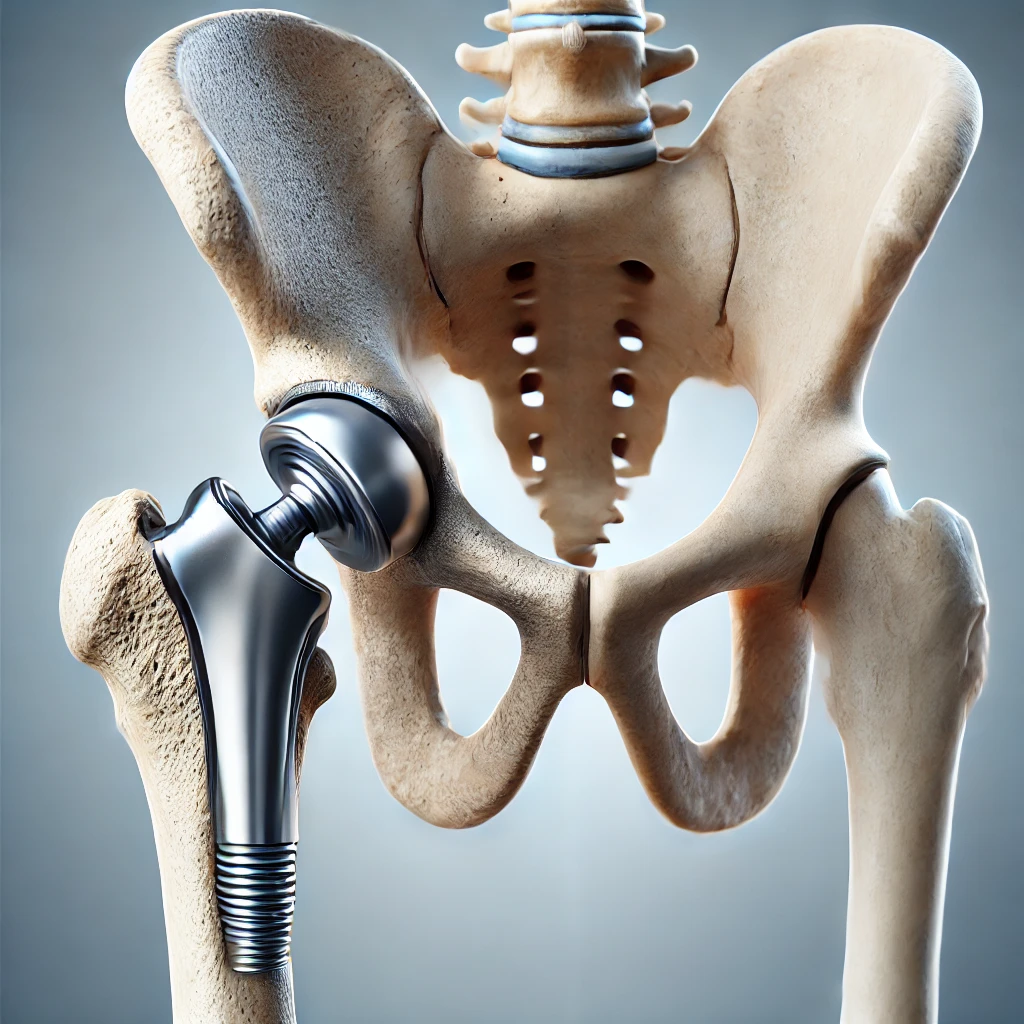

تعویض مفصل لگن

روش جراحی برای جایگزینی مفصل آسیب دیده با پروتز مصنوعی است که درد را کاهش داده و حرکت را بهبود می‌بخشد.